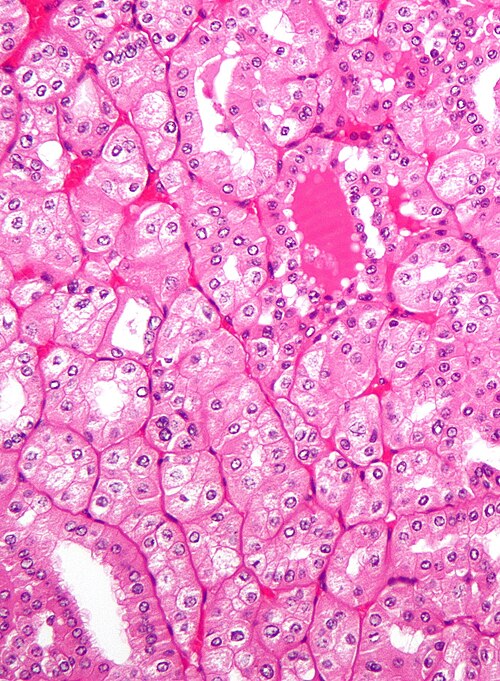

Chromophobe renal cell carcinoma, eosinophilic variant - high mag.jpg

Chromophobe renal cell carcinoma (eosinophilic)